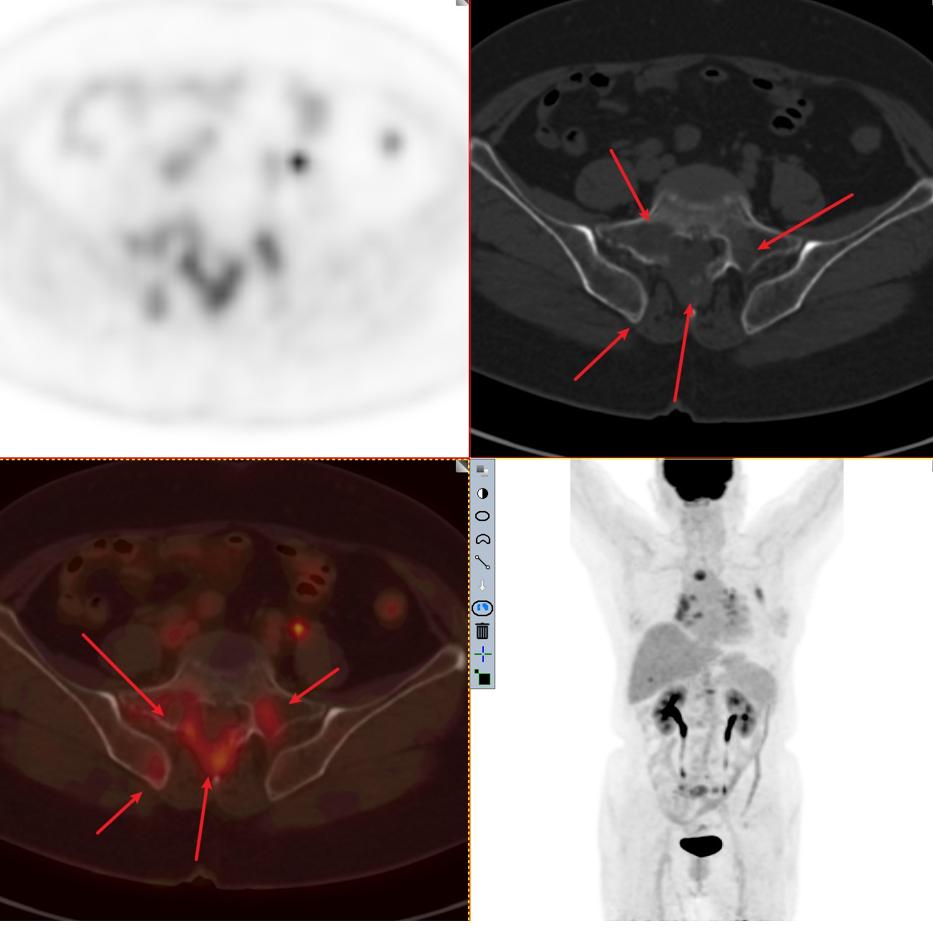

患者2:图5

患者2:图6

图4-5分别提示:胸骨、腰椎、骶骨及右侧髂骨骨转移。

因此该患者的肿瘤分期与第一位患者截然不同,同样病灶都在3cm以内,该患者属于T1cN3M1c 属于ⅣB期 最晚一期。这例患者当然不能手术了,只有寄希望于基因检测,如果有匹配的靶向药物,结合全身化疗或者免疫治疗,有一部分人还是有不错的效果。